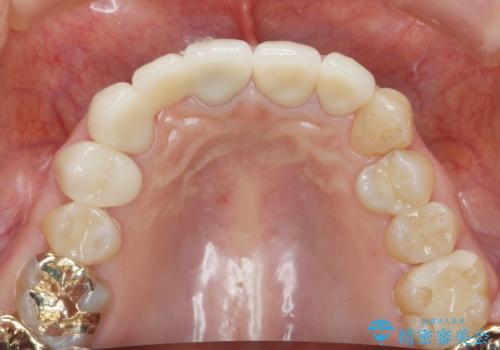

大きな穿孔が見られた、右上側切歯の抜去をこないブリッジの設計を含めた前歯の審美性の改善を目的とするセラミック治療を行いました。

- 66万円(ジルコニアクラウン×5・仮歯×5)費用は治療当時の料金となります

自然な歯の色調や仕上がりに大変満足いただけました。